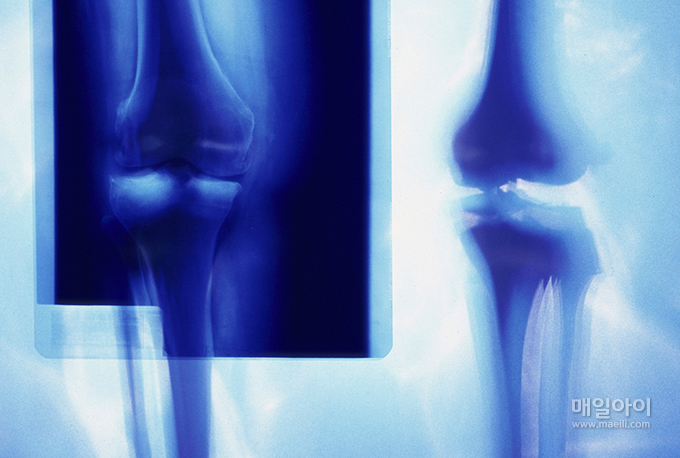

관절이 빠진 것을 말합니다. 골절과 마찬가지로 다친 관절 주위의 조직이 동시에 상한 경우가 많습니다.

특히 혈액 순환이 나빠져서 통증, 부종이 오고 관절 움직임이 나빠집니다. 시간이 지날 수록 관절 주위의 부종이 심해지고 탈구의 교정이 어려워집니다. 반드시 병원에서 치료해야 합니다.